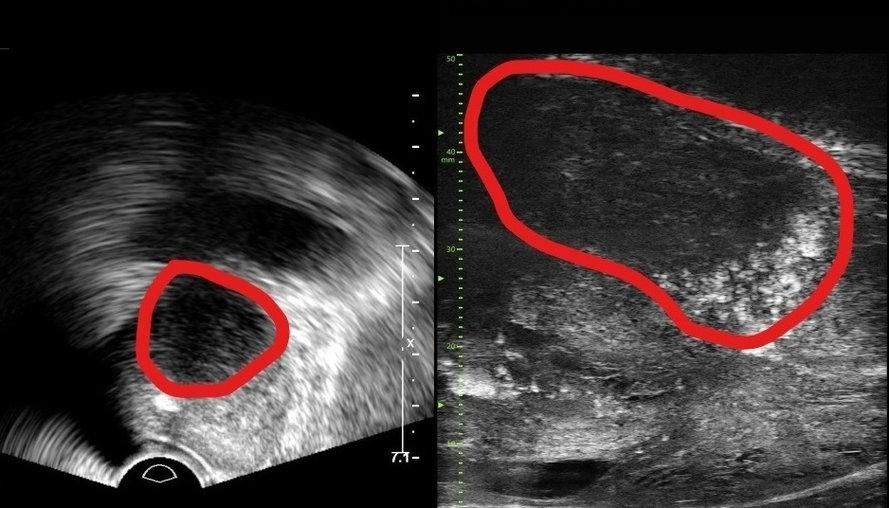

기존 전립선 초음파 사진(좌) 및 최신 초음파 사진(우).

분당서울대병원 비뇨의학과는 기존 초음파보다 3배 더 높은 해상도의 실시간 영상을 통해 전립선 종양 평가가 가능한 마이크로 초음파 장비를 국내 최초로 도입했다고 24일 밝혔다.

29MHz 마이크로 초음파를 사용하는 이 장비는 전립선과 주변의 해부학적 구조를 선명히 표시하고 표적 조직검사를 유도한다. 의심 영역을 실시간으로 확인하면서 전립선 조직의 미세한 변화와 병변을 식별하고 조직검사 채취를 위한 바늘을 정확한 위치에 삽입할 수 있다는 장점이 있다.

기존의 경직장 초음파는 해상도가 낮아 전립선 종양, 특히 작은 암 병변을 감지하는 데 한계가 있었다. 하지만 마이크로 초음파의 높은 해상도와 실시간 영상의 시각화는 자기공명영상(MRI)으로 발견할 수 없는 전립선암을 찾을 때도 충분히 기여할 것으로 기대하고 있다. MRI 검사 보다 환자의 신체적, 심리적, 경제적 부담도 적을 수밖에 없다.